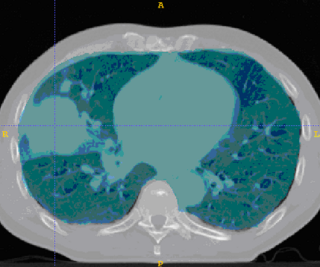

This example shows anatomic change in the thorax. The patient has a collapsed left lower lobe in the pre-treatment scan (top), which has recovered in the mid-treatment scan (bottom). Notice there is some kind of fluid accumulation below the collapsed lung.